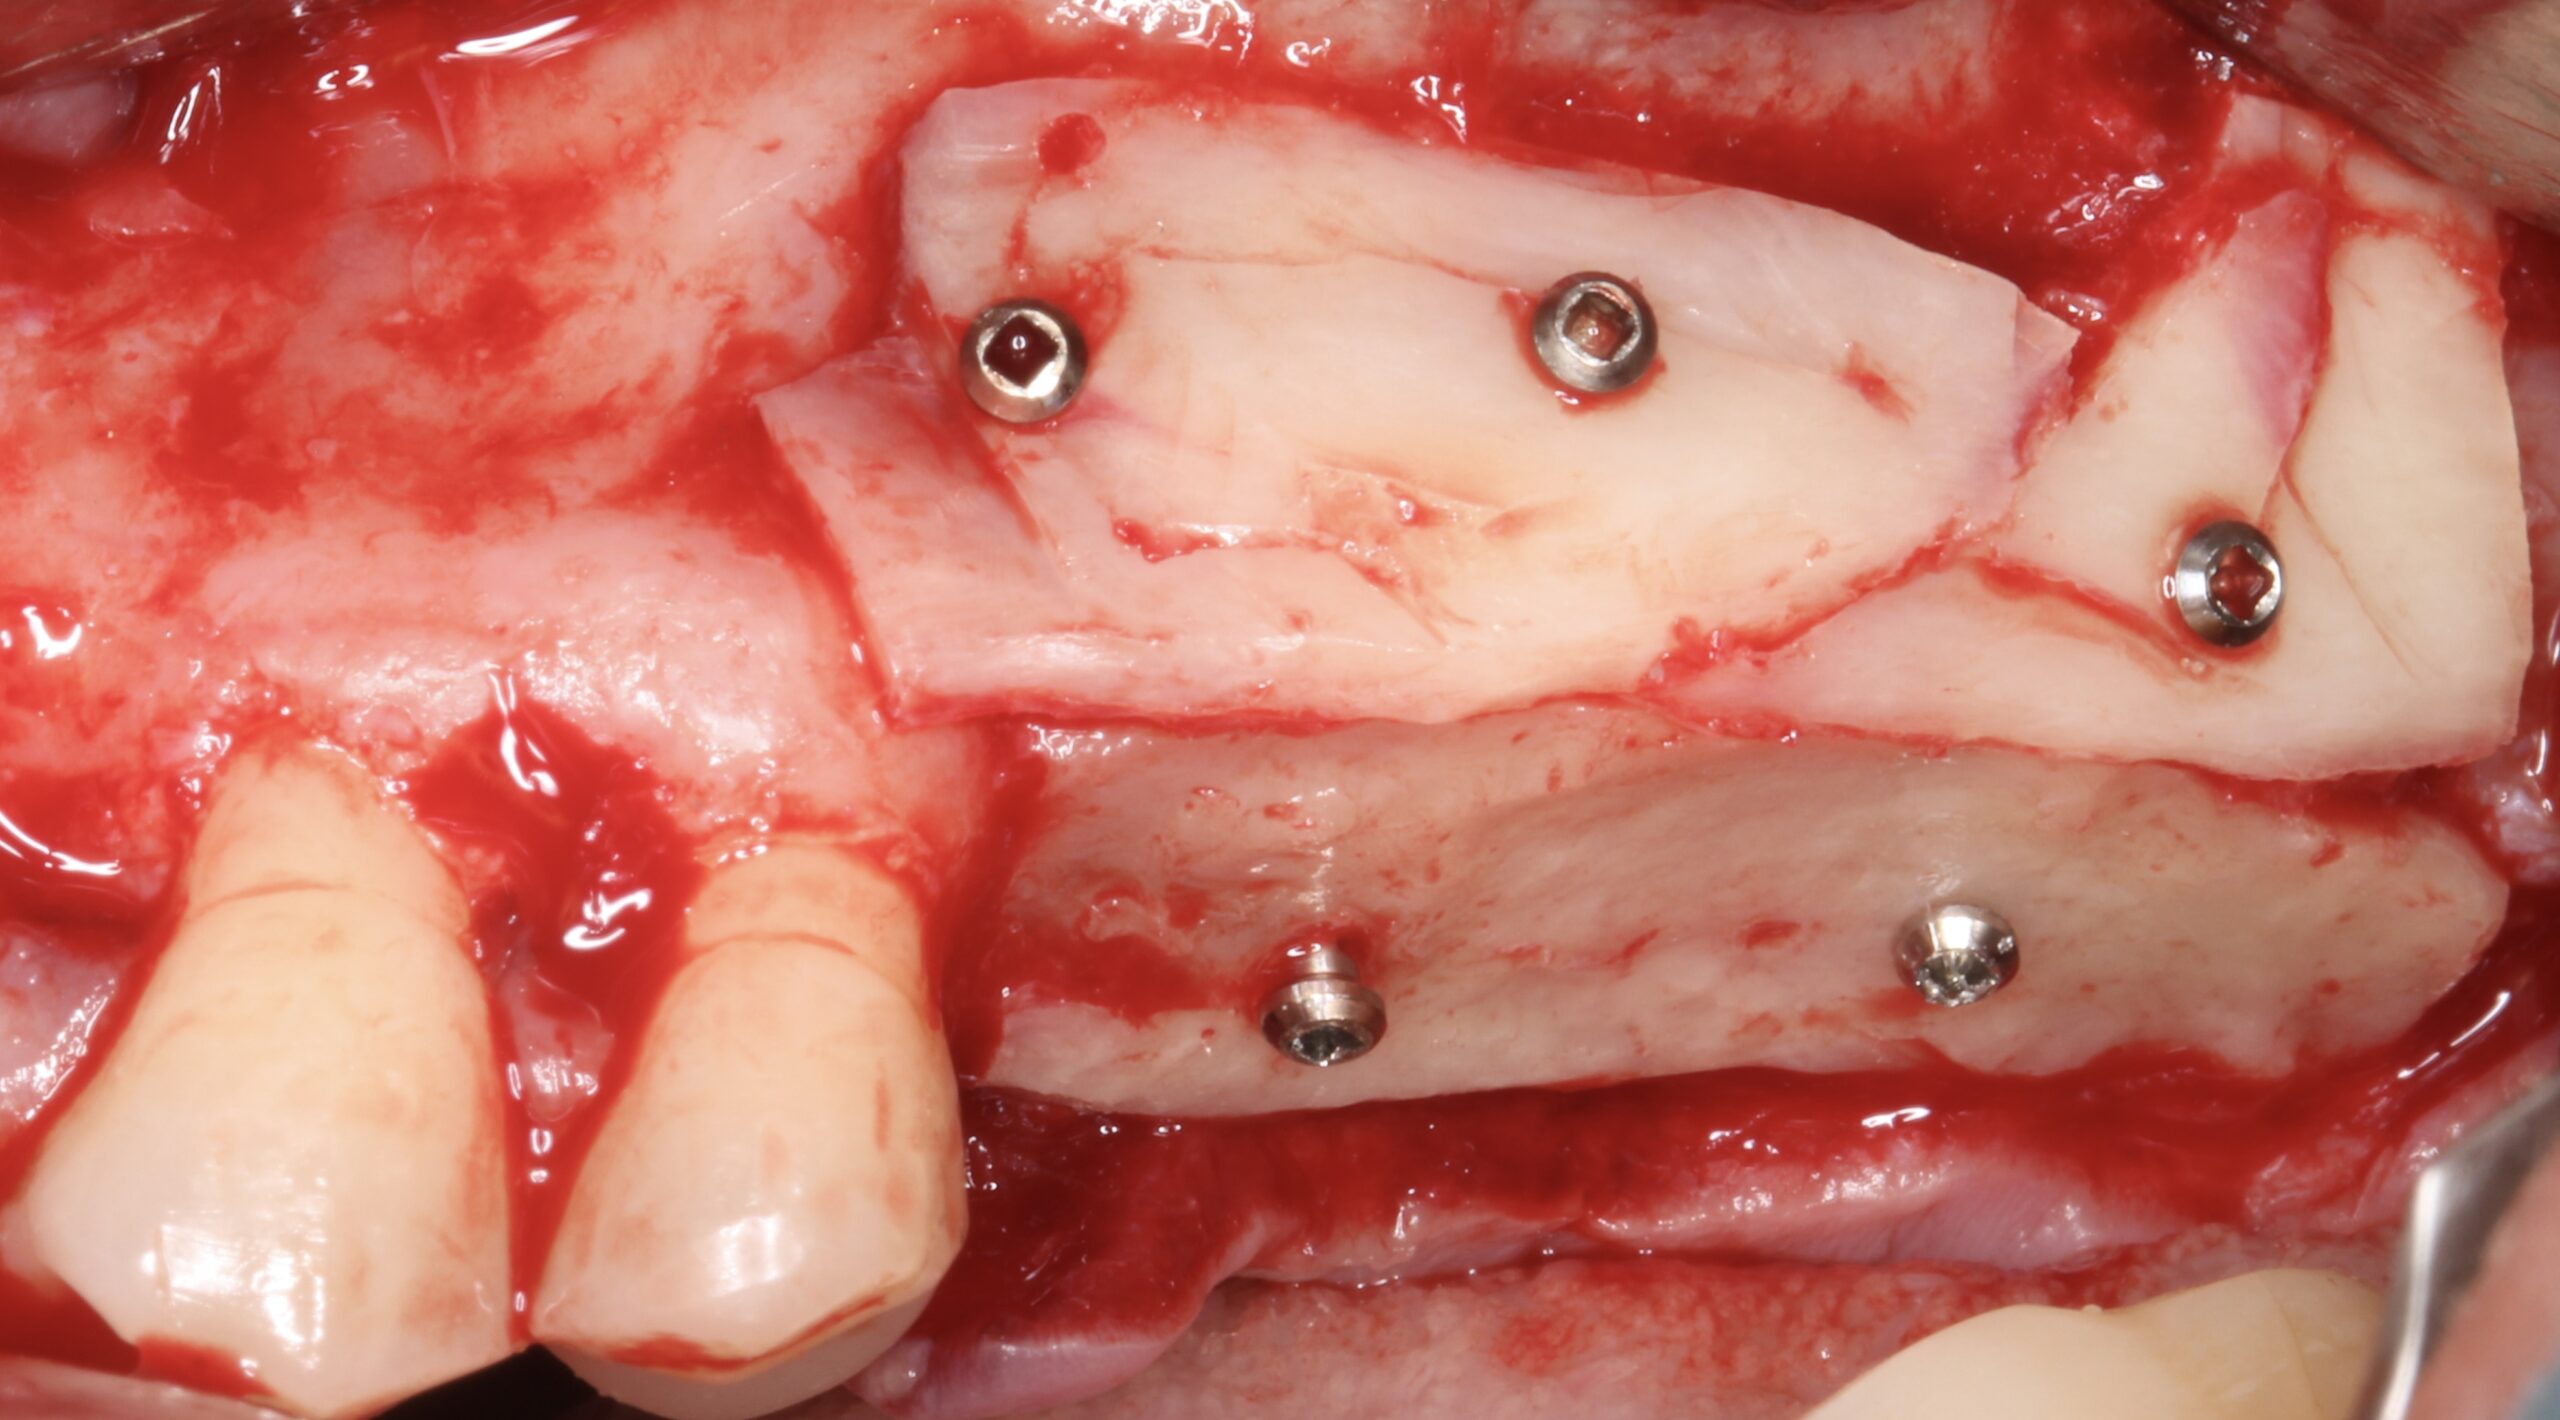

Figure 5.

A split bone block was fixed by screws at the coronal aspect of the alveolar ridge from peak to peak.

Figure 6.

The gap between the block and the alveolar ridge was filled with scraped bone chips.

Figure 7.

Another split block was used to cover the exposed scraped bone chips.

Figure 8.

Coronal view of the bone graft.